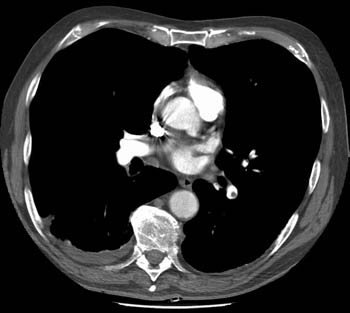

Massive Pulmonary Embolism

By

Scott Williams

August 28, 2001